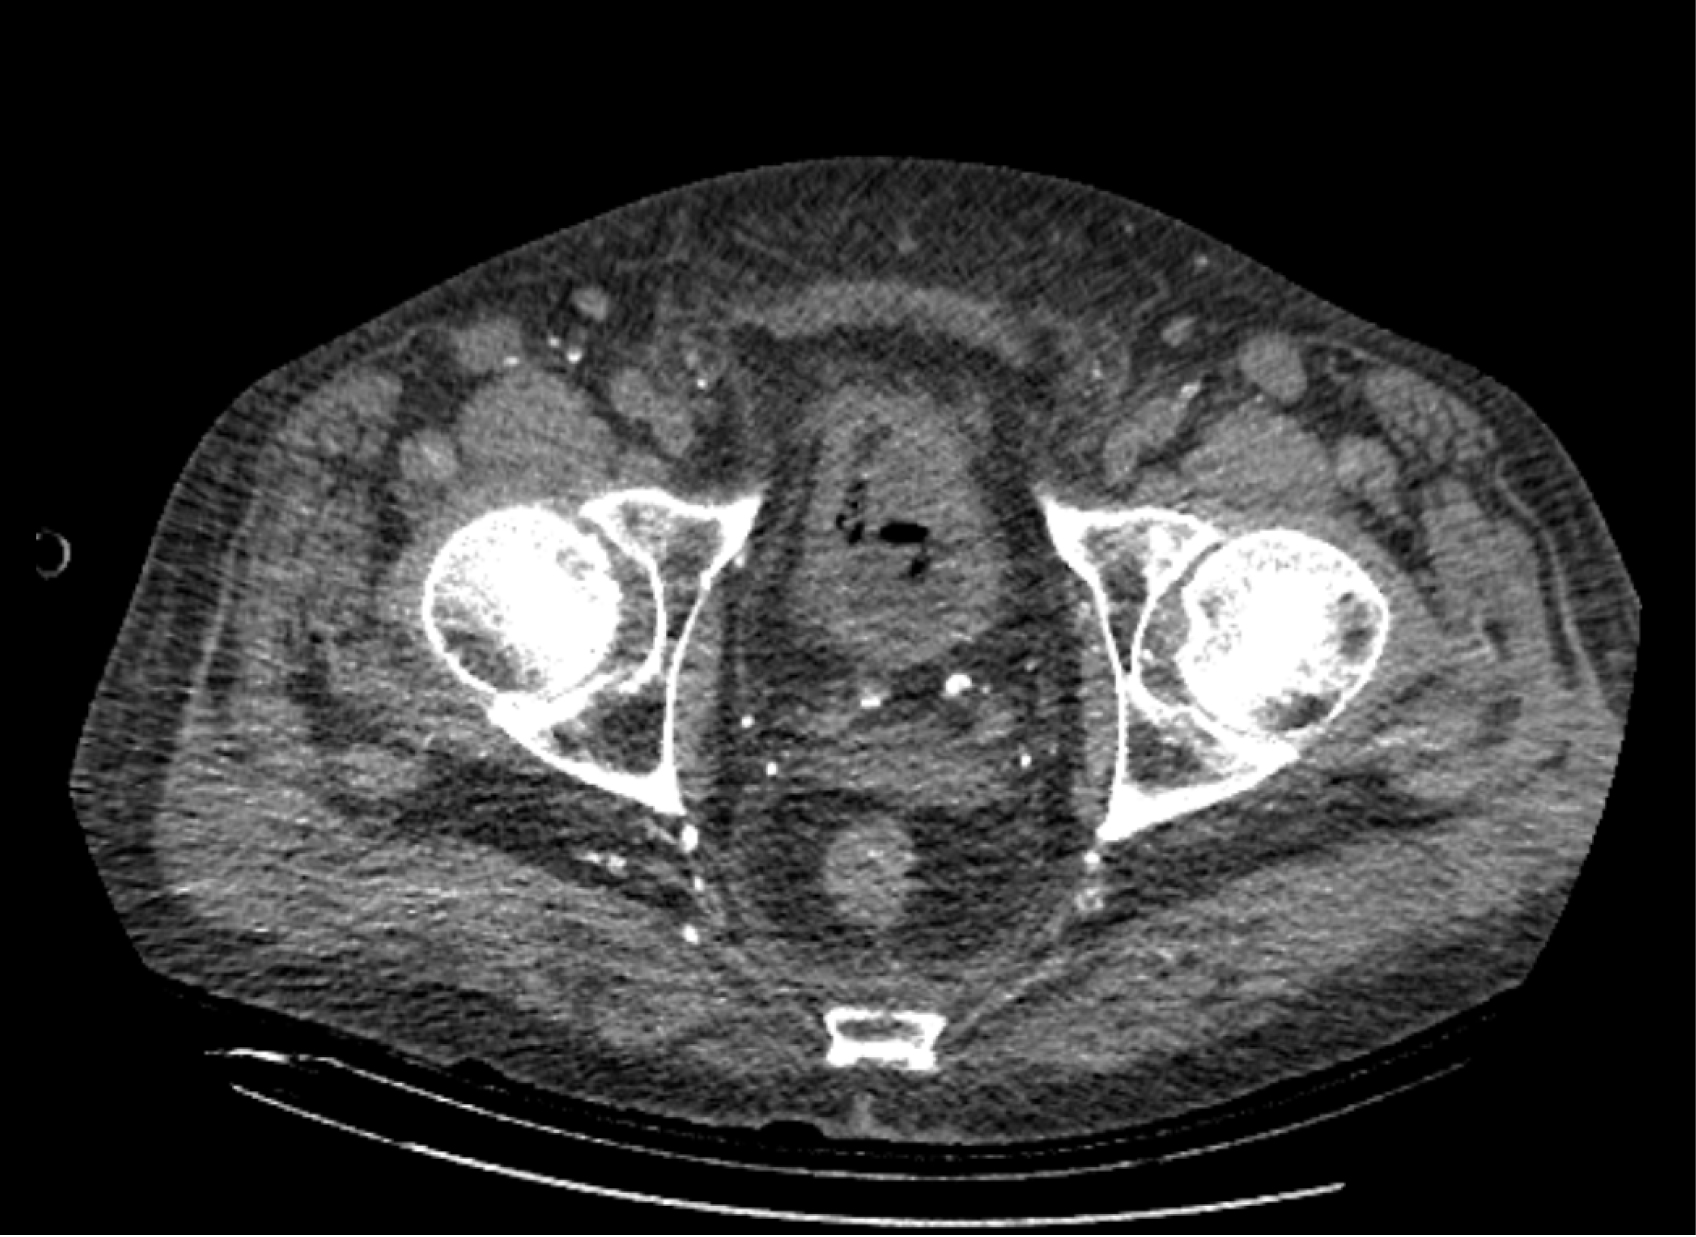

На следующий день состояние пациента оставалось тяжелым, с отрицательной динамикой, креатинин сыворотки возрос до 735,2 ммоль/л, Появились жалобы на слабость, тошноту. При осмотре: живот мягкий, вздут по всем отделам, при пальпации болезненный. Область почек не изменена, при пальпации безболезненна, патологических изменений в области почек не выявлено. Симптом поколачивания отрицательный билатерально. При УЗИ были обнаружены плевральный выпот по 300–400 мл с каждой стороны, гепатомегалия, увеличение размеров селезенки, асцит. Кроме того, в обеих почках были визуализированы тени, характерные для конкрементов. По данным компьютерной томографии (КТ) конкрементов не обнаружено, но в лоханке, на всем протяжении левого мочеточника и, частично, в правом мочеточнике, а также в мочевом пузыре визуализировался газ (рис. 1–6).

Рис. 6. Компьютерная томография органов брюшной полости, забрюшинного пространства, органов малого таза. Газ в верхнем полюсе левой почки